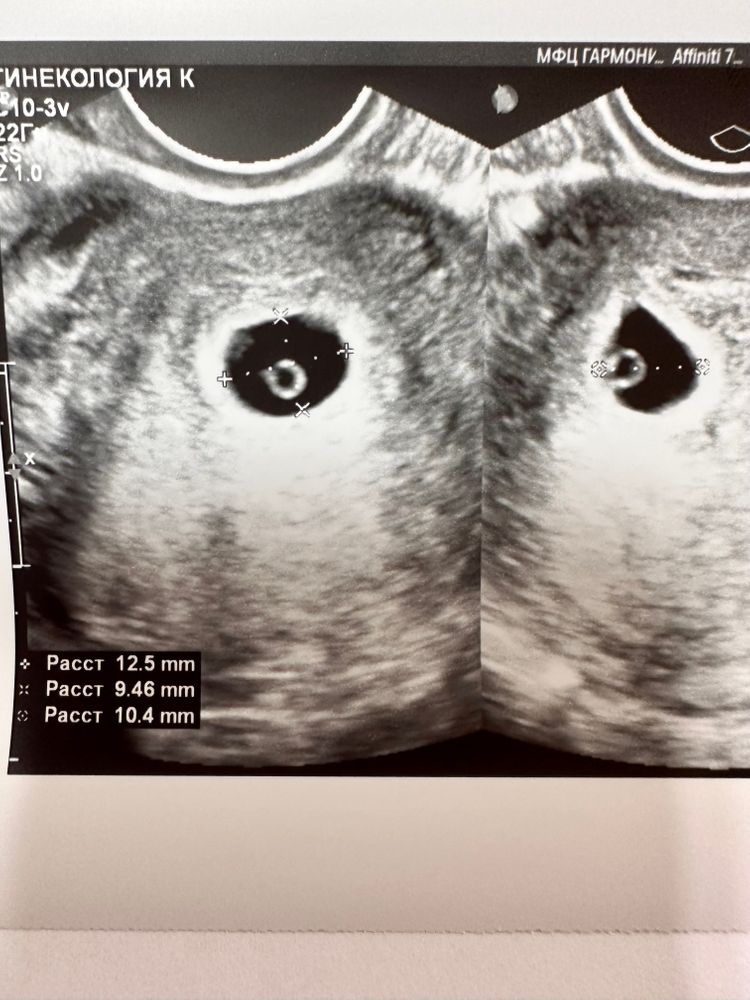

Вот как выросли за 6 дней с прошлого Узи.